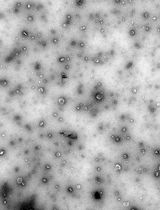

This protocol describes the isolation and flow cytometric analysis of extracellular vesicles (EVs) derived from red blood cells, endothelial cells, and platelets in human peripheral blood. The protocol includes steps for preparing platelet-free plasma, fluorescent antibody staining, gating strategies, and technical controls. This protocol was developed within a study on EV release in snakebite-associated thrombotic microangiopathy; the protocol addresses challenges such as variable autofluorescence and heterogeneity in EV origin. It is flexible and can be adapted for alternative antibody panels targeting different cell populations or EV subtypes, including leukocyte-derived EVs.

EVs play important roles in health and disease, but their small size, heterogeneity, and variable autofluorescence make analysis challenging [2]. Several techniques have been developed for EV analysis, including electron microscopy, nanoparticle tracking analysis, tunable resistive pulse sensing, western blotting, and ELISA-based assays, each with advantages and limitations [1]. Existing EV isolation protocols, including ultracentrifugation, precipitation, and size-exclusion chromatography, often face challenges such as incomplete removal of contaminating platelets, co-isolation of protein aggregates, variable EV recovery, and loss of vesicles during multiple washing steps [3]. Moreover, differences in centrifugation speeds, buffer preparation, and gating strategies limit reproducibility across laboratories [4]. Flow cytometry–based detection adds further complexity due to EV heterogeneity, variable autofluorescence, and the difficulty of distinguishing true EVs from debris [5].